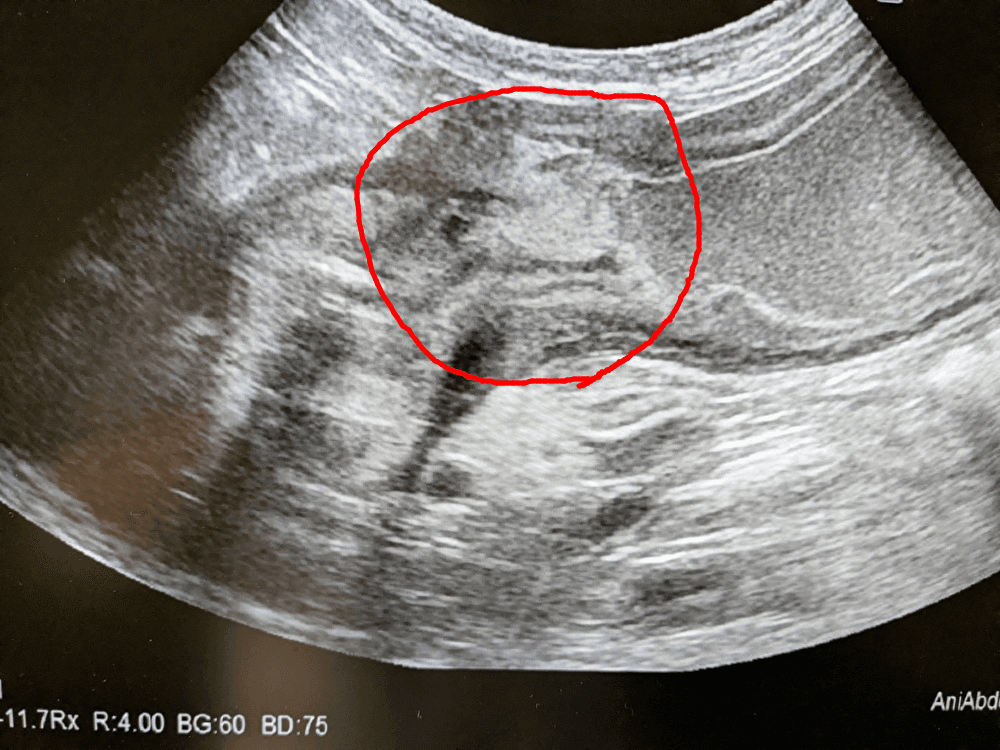

診断は腹部超音波検査および造影レントゲン検査にて可能です。

超音波検査です。丸で囲った場所が狭窄部位で、その右側が胃の内腔です。流れなくなった食渣が溜まっています。